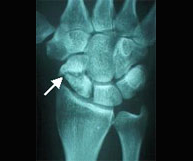

El paciente de edad se beneficia habitualmente del tratamiento conservador con escayola. En el paciente joven el desplazamiento suele ser difícilmente manejable con inmovilización con yeso por lo que es frecuente la realización de una pequeñaintervención para la recuperación anatómica de la muñeca pudiendo reincorporarse a su actividad habitual en el menor tiempo posible y con el menor riesgo de complicaciones.Dentro de la región anatómica de la muñeca se encuentran los huesos del carpo. El hueso escafoides es el que se fractura con más frecuencia tras caídas sobrela mano en extensión. Es por ello una lesión característica en deportes como motociclismo, ciclismo y patín donde se pueden sufrir traumatismos a gran velocidad. El dolor se localiza siguiendo el eje del pulgar pero a nivel de la muñeca y el dolor a la palpación en esta zona (tabaquera anatómica) es extremo. Las fracturas desplazadas se suelen estabilizar quirúrgicamente sin cicatriz,a través de la introducción percutánea de un tornillo intraóseo que permite el inicio de la movilización de la articulación inmediatamente.